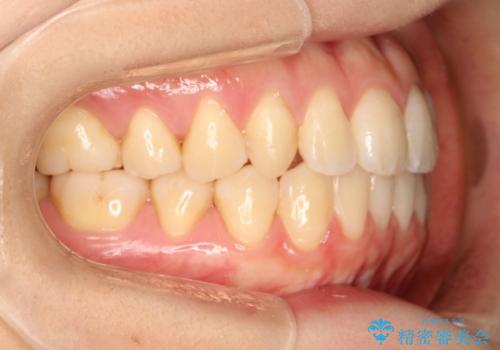

初診時の歯並びの状態としては、上下ともに前歯部に限局した軽度ののがたつき(叢生)がある状態でした。

主に歯列弓の拡大とディスキング(歯と歯の間に隙間を作る処置)を行い叢生を改善しました。

見た目、嚙み合わせ及び、治療期間や施術内容に大変ご満足いただきました。